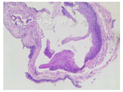

根据持续声嘶症状,嗓音粗糙度中度,频闪喉镜检查可见右侧声带囊样新生物,病变黏膜波减退,诊断右侧声带囊肿,咽喉反流性疾病。在全麻下行支撑喉镜下显微镜辅助声带囊肿切除术,围手术期配合气流轻声发声训练指导及抗反流治疗。术中见右侧声带前中交界处有一囊肿样物,淡黄色,表面光滑,基地较宽,活动度稍差;采用显微中间微瓣法行声带囊肿剥离手术:显微喉镰刀行囊肿黏膜旁纵切口,并用30°喉显微剥离子行囊肿黏膜下剥离,见囊肿深及声带的系膜层,牵拉囊壁,完整剥离囊肿,并用显微喉剪行囊肿根部切除,将声带黏膜复位。术后予激素雾化、质子泵抑制剂抗反流、喉部微波理疗等处理,绝对禁声3 d,气流轻声发声1周。术后病理示:符合声带囊肿(图2)。